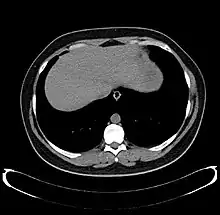

The diagnosis of liver disease is made by liver function tests, groups of blood tests, that can readily show the extent of liver damage. If infection is suspected, then other serological tests will be carried out. A physical examination of the liver can only reveal its size and any tenderness, and some form of imaging such as an ultrasound or CT scan may also be needed.

Axial CT image showing anomalous hepatic veins coursing on the liver's subcapsular anterior surface[66]

Axial CT image showing anomalous hepatic veins coursing on the liver's subcapsular anterior surface[66] Maximum intensity projection (MIP) CT image as viewed anteriorly showing the anomalous hepatic veins coursing on the anterior surface of the liver

Lateral MIP view in the same patient as previous image A CT scan in which the liver and portal vein are shown

A CT scan in which the liver and portal vein are shown